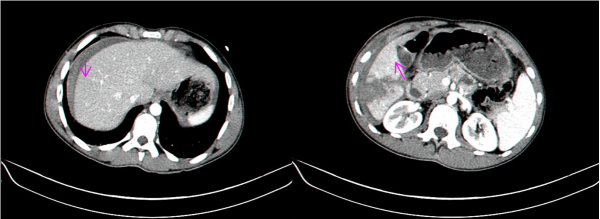

- טומוגרפיה ממוחשבת - בדיקה זו יכולה להראות את היקף הנזק ומיקומו. בדיקה זו אפשר לבצע בחולים שהם יציבים המודינמית, והיא בדיקת הבחירה (תצלום 7.10 ). ניתן להדגים גם דימום פעיל מהכבד על ידי הדגמת דליפה של חומר ניגוד באזור החבלה (תצלום 8.10).

בנוסף ב- CT אפשר לראות גם פגיעות באיברים אחרים (תצלום 9.10) כולל כלי דם (תצלום 10.10).